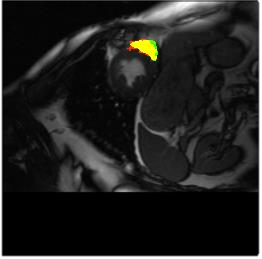

Deep Convolutional Neural Networks (DCNNs) are used extensively in biomedical image segmentation. However, current DCNNs usually use down sampling layers for increasing the receptive field and gaining abstract semantic information. These down sampling layers decrease the spatial dimension of feature maps, which can be detrimental to semantic image segmentation. Atrous convolution is an alternative for the down sampling layer. It increases the receptive field whilst maintains the spatial dimension of feature maps. In this paper, a method for effective atrous rate setting is proposed to achieve the largest and fully-covered receptive field with a minimum number of atrous convolutional layers. Furthermore, different atrous blocks, shortcut connections and normalization methods are explored to select the optimal network structure setting. These lead to a new and full-scale DCNN - Atrous Convolutional Neural Network (ACNN), which incorporates cascaded atrous II-blocks, residual learning and Fine Group Normalization (FGN). Application results of the proposed ACNN to Magnetic Resonance Imaging (MRI) and Computed Tomography (CT) image segmentation demonstrate that the proposed ACNN can achieve comparable segmentation Dice Similarity Coefficients (DSCs) to U-Net, optimized U-Net and hybrid network, but with significantly reduced trainable parameters due to the use of full-scale feature maps and therefore computationally is much more efficient for both the training and inference.